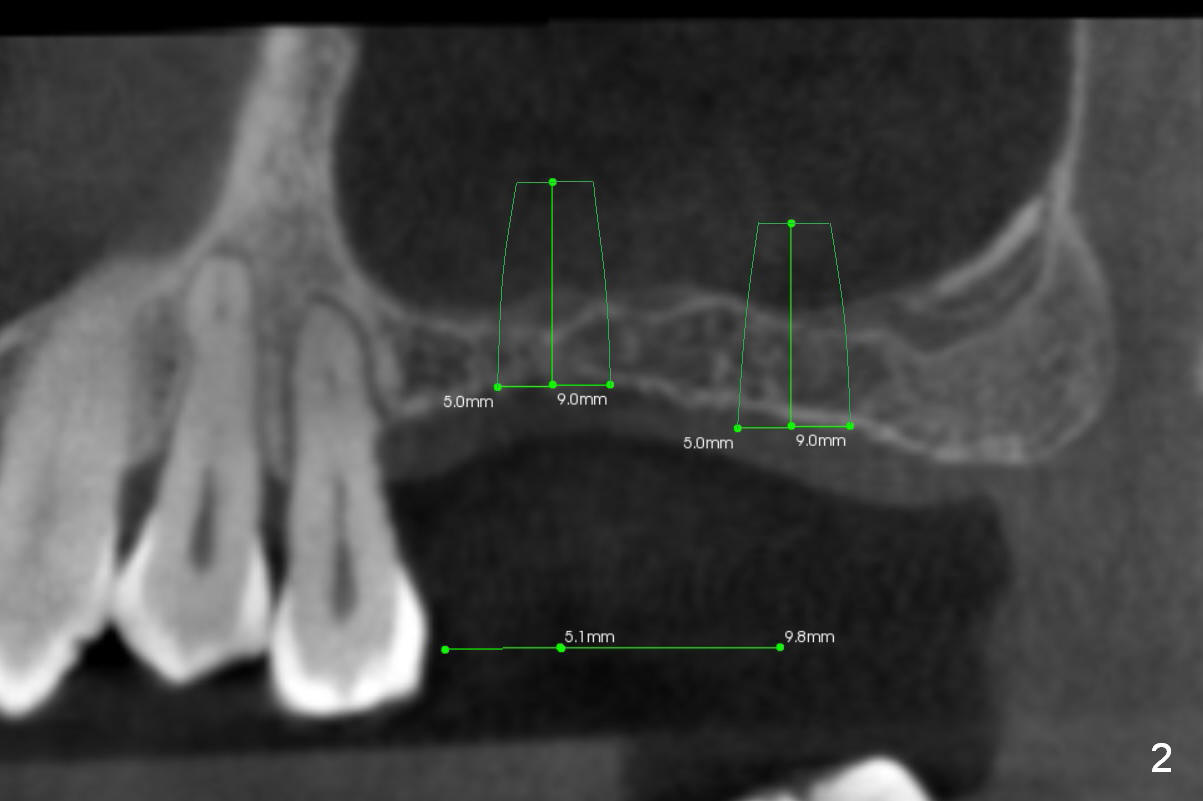

Although the patient agrees to have the tooth #13 with mobility II removed, implants at #14 and 15 should help alleviate occlusal trauma to the former. Initial osteotomy depth will be 1 and 2 mm at #14 and 15 (Fig.1: 1-2 mm from the sinus floor), followed Magic Sinus Lifter and bone graft. Implants to be placed are going to be 5x9 (at #15) or 5x7 (at #14) mm (Fig.2,3). Abutments (6x4(2) mm) will be placed if primary stability is achieved. Prepare torque wrench and the adaptor to measure torque value. Immediate splinted provisional is to be fabricated with occlusal reduction at #13.